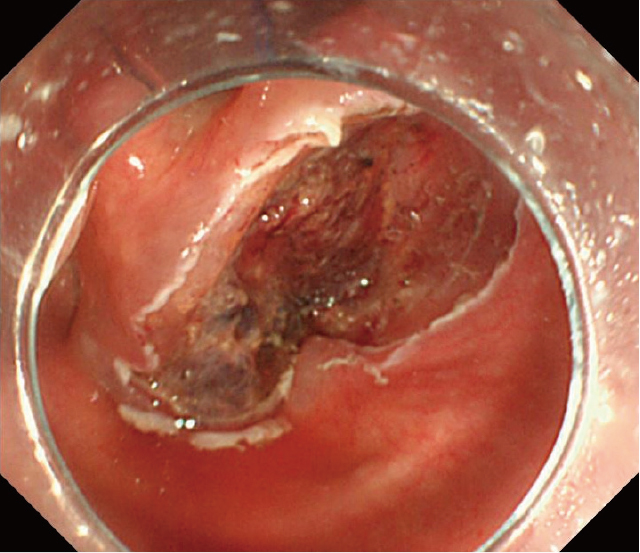

治療経過:画像検査所見より咽頭脂肪腫と診断した.窒息の可能性の回避のため切除が必要と判断し,耳鼻咽喉科の協力の下,ESDを施行した.彎曲型喉頭鏡にて喉頭展開したところ,腫瘍の基部は輪状後部と右梨状陥凹に認め,食道入口部まで十分に観察可能であった(Figure 6).ヒアルロン酸入り局注液で膨隆を得た後,1.5mmのDual knife(オリンパス社製)を用いて病変肛門側である食道入口部の9時方向から切開を開始し,次いで6時方向(輪状後部側),3時方向(右梨状陥凹側),12時方向(披裂側)の順に切開をつなげ全周切開とした.上皮下剝離時,腫瘍の披裂~梨状陥凹側は脂肪が多く血管が目立ったが,通常のESDと同様に一括切除可能であった(Figure 7).術後経過は良好で翌日より食事を開始した.痛みはアセトアミノフェンの内服でコントロール可能で術後4日で退院となった.術後2週間の外来時には痛み,嗄声共になく術後2カ月の内視鏡ではESD潰瘍は治癒し瘢痕化していた(Figure 8).また,患者本人の嚥下時違和感も消失していた.

ESD後の潰瘍底.通常のESD同様,一括切除が可能であった.